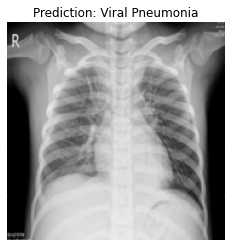

Currently, there is an urgent need for efficient tools to assess the diagnosis of COVID-19 patients. In this project, we propose a constructive solution for detecting and labeling infected tissues on CT lung images of such patients. To cut down false positives our model is trained on 4 types of lung CT images : COVID, Viral Pneumonia, Lung Opacity and normal images to get the best possible results with highest accuracy.